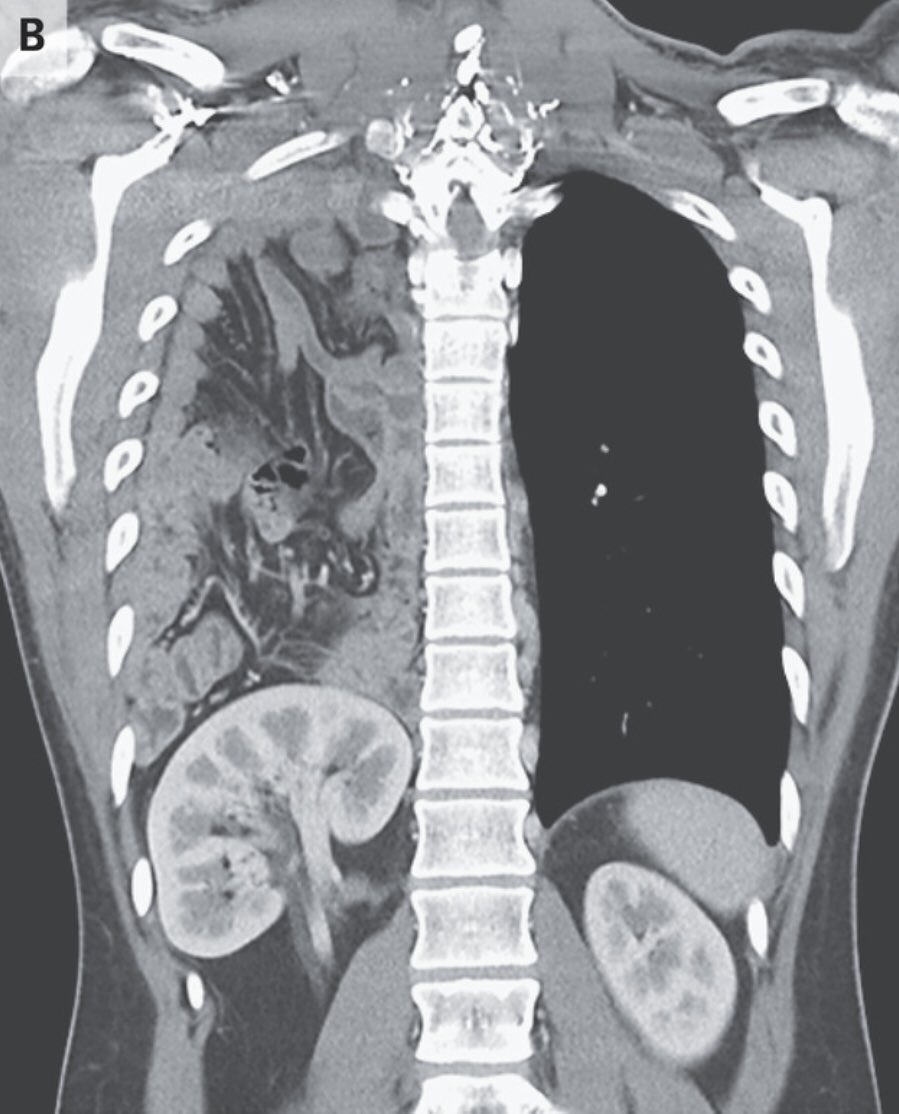

و النص اليمين من الحجاب الحاجز طالع لفوق شوية جهة الصدر (elevated right hemidiaphragm)

القولون كان قاعد في فوق في محل ما محلو (translocation of the colon into the right upper quadrant of the abdomen)

و السبب هو عيب خُلقي في الحجاب الحاجز

التشخيص الإتعمل للشاب دا هو انو عندو فتق بوكدالك، او فتق حجابي خلقي

congenital diaphragmatic hernia due to a posterolateral diaphragmatic defect-Bochdalek hernia

في العادة العيانيين بيتعرفو و بيتشخصو صغار عشان الاعراض البيعملها الفتاق

في حالات نادرة ممكن تكون من غير اعراض و المريض يكبر بيها و عندها العرض الممكن يجي بيه العيان هو انسداد معوي